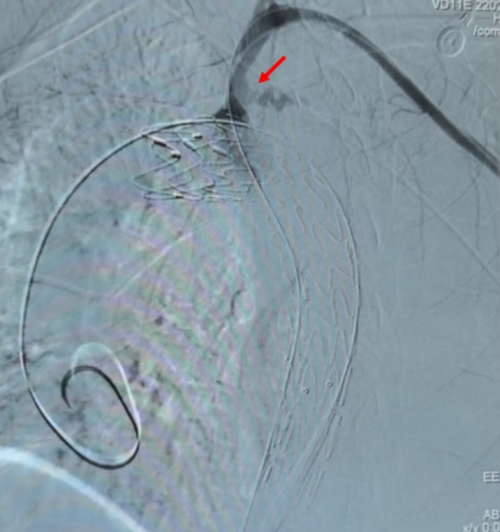

左锁骨下动脉造影:左锁骨下动脉近端血管破裂,血流喷出。

面对如此严峻的情况,赵扬程及介入团队迅速将球囊通过右侧股动脉输送至左侧锁骨下动脉,并根据CT图像经验性封堵破口。在破口封堵以及各种抢救措施的共同作用下,患者终于恢复了自主心率及血压。由于患者左锁骨下动脉破口距离主动脉太近,单纯应用覆膜支架覆盖破口,有手术失败的风险。赵扬程团队决定,再穿刺左侧股动脉,为患者植入胸主动脉覆膜支架以覆盖左锁骨下动脉开口,并穿刺左侧肱动脉进行左锁骨下动脉根部栓塞。经过这一系列复杂精准的操作,患者的生命体征逐渐平稳。